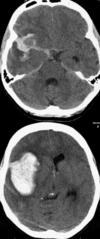

Du er KBU-læge i modtagelsen og modtager tidligt om morgenen en 73-årig herre, der sidst er set rask aftenen før klokken 22.30. Han er blevet fundet i sengen af hustruen med svær venstresidig hemiparese, da hun har vækket ham med morgenmad på sengen.

Efter aftale med radiologen bliver der foretaget en CTscanning af cerebrum uden IV-kontrast.

Hvad er den mest sandsynlige diagnose ud fra anamnese, klinik og fund på CTscanning?

a. Intet abnormt, normalvariant med forkalkning i basalganglierne på højre side

b. Parenkymblødning på baggrund af hypertension

c. Iskæmisk infarkt

d. Højresidig tumor

e. Højresidig tumor

Du er KBU-læge i modtagelsen og modtager tidligt om morgenen en 73-årig herre, der sidst er set rask aftenen før klokken 22.30. Han er blevet fundet i sengen af hustruen med svær venstresidig hemiparese, da hun har vækket ham med morgenmad på sengen.

Efter aftale med radiologen bliver der foretaget en CTscanning af cerebrum uden IV-kontrast.

Hvad er den mest sandsynlige diagnose ud fra anamnese, klinik og fund på CTscanning?

a. Intet abnormt, normalvariant med forkalkning i basalganglierne på højre side

b. Parenkymblødning på baggrund af hypertension

c. Iskæmisk infarkt

d. Højresidig tumor

e. Højresidig tumor